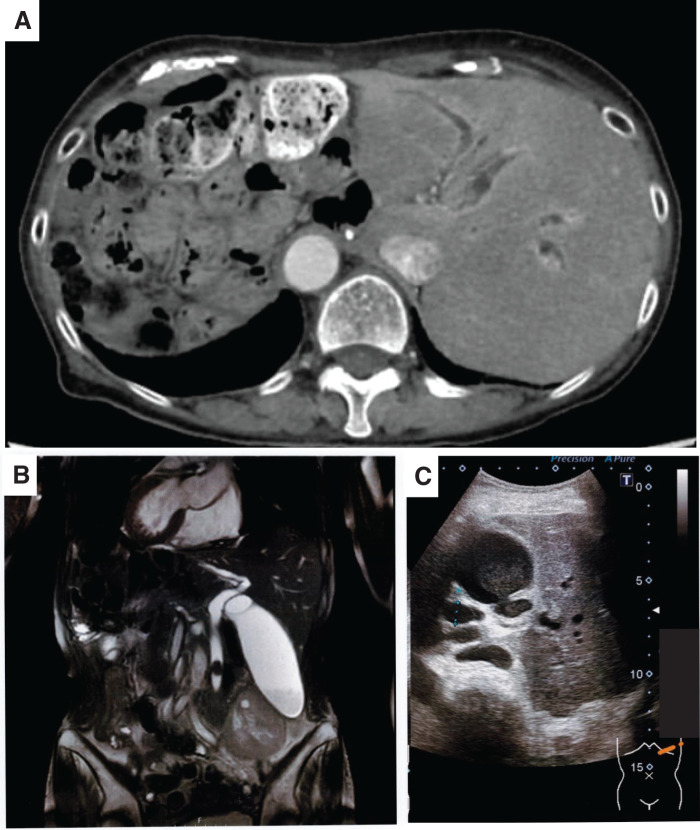

A 70-year-old female with a known history of SIT and prior total gastrectomy with R-Y reconstruction presented with fever and left upper quadrant abdominal pain. Laboratory tests revealed elevated inflammatory markers and cholestatic liver enzymes. Imaging confirmed choledocholithiasis with upstream biliary dilation in a mirror-image anatomical setting (Fig. 1). Initial management included broad-spectrum antibiotics and biliary decompression. ERCP was attempted by the gastroenterology team; however, it failed because the long Roux limb and dense postoperative adhesions prevented the endoscope from reaching the papilla. Therefore, the patient was referred to the surgical department. After the patient’s informed consent was obtained, we planned a 2-stage approach consisting of laparoscopic cholecystectomy followed by LCBDE.

From a diagnostic perspective, situs inversus can delay the identification of biliary disease because of atypical symptom localization.2,3) Patients frequently exhibit left-sided upper abdominal pain rather than the typical right-sided pain seen in orthotopic anatomy. In our case, recurrent cholangitis was ultimately confirmed via imaging, which showed choledocholithiasis in the mirror-image anatomy.